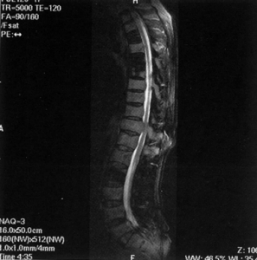

本片為“十五”國家重點音像出版規劃品種、衛生部醫學視聽教材。包括如下內容:1.腹部血管造影的方法,主要講述腹主動脈造影、選擇性動脈造影、超選擇性動脈造影、下腔靜脈造影的操作。2.腹部血管的正常造影表現。3.腹部常見疾病的血管造影表現,包括肝癌、肝血管瘤、胰島細胞瘤、下消化道出血、腎癌、腎臟錯構瘤、腎動脈狹窄、腹主動脈瘤、下腔靜脈阻塞等。本片由河北醫科大學製作,片長45分鐘,適合醫學生和臨床醫師使用。

注入碘系造影劑,染色肝臟、膽囊、胰臟、腎臟、腸等腹部臟器的血管,然後做連續X光攝影,探索血管的形狀變化與異常的檢查。做血管檢查時,若已做完其他影像診斷法仍覺不足,可實施腹部血管造影檢查。對於消化道出血部位的診斷、治療,或判別各臟器的腫瘤是屬良性或惡性,此檢查皆能發揮良好功效。若腫瘤屬惡性,此檢查還能讓醫師了解疾病的範圍,及適不適合動手術。

①診斷腹部臟器與血管的疾病;②決定適不適合動手術及手術的方法與範圍。

○本檢查所能發現的疾病